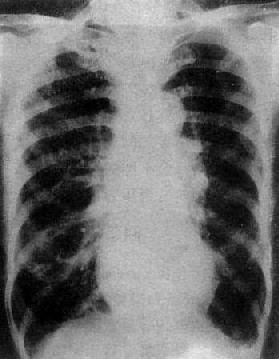

单纯二尖瓣狭窄X线表现(图3-2-15)为:①心脏增大,左心房和右心房增大,左心耳常明显增大;②主动脉球缩小,主要原因是左心室血液排出量减少,主动脉发育障碍或心和大血管向左旋转时,主动脉弓折叠;③左心室缩小,心尖位置上移,心左缘下段较平直;④二尖瓣瓣膜钙化,系直接征象;⑤肺瘀血和间质性水肿。上肺静脉扩张,下肺静脉变细。有时还可见肺野内出现直径1~2mm大小的颗粒状影,为含铁血黄素沉着。

图3-2-15 二尖瓣狭窄

A.右前斜位:右心室增大,肺动脉段突出(↑),心前间隙变窄(↑),左心房轻度增大;B.后前位:心增大,呈二尖瓣型,右心室增大,肺动脉段突出,左心耳增大,出现第三弓(↓),有肺瘀血表现;C.左前斜位:右心室增大,左心房增大不明显;左心室不增大。